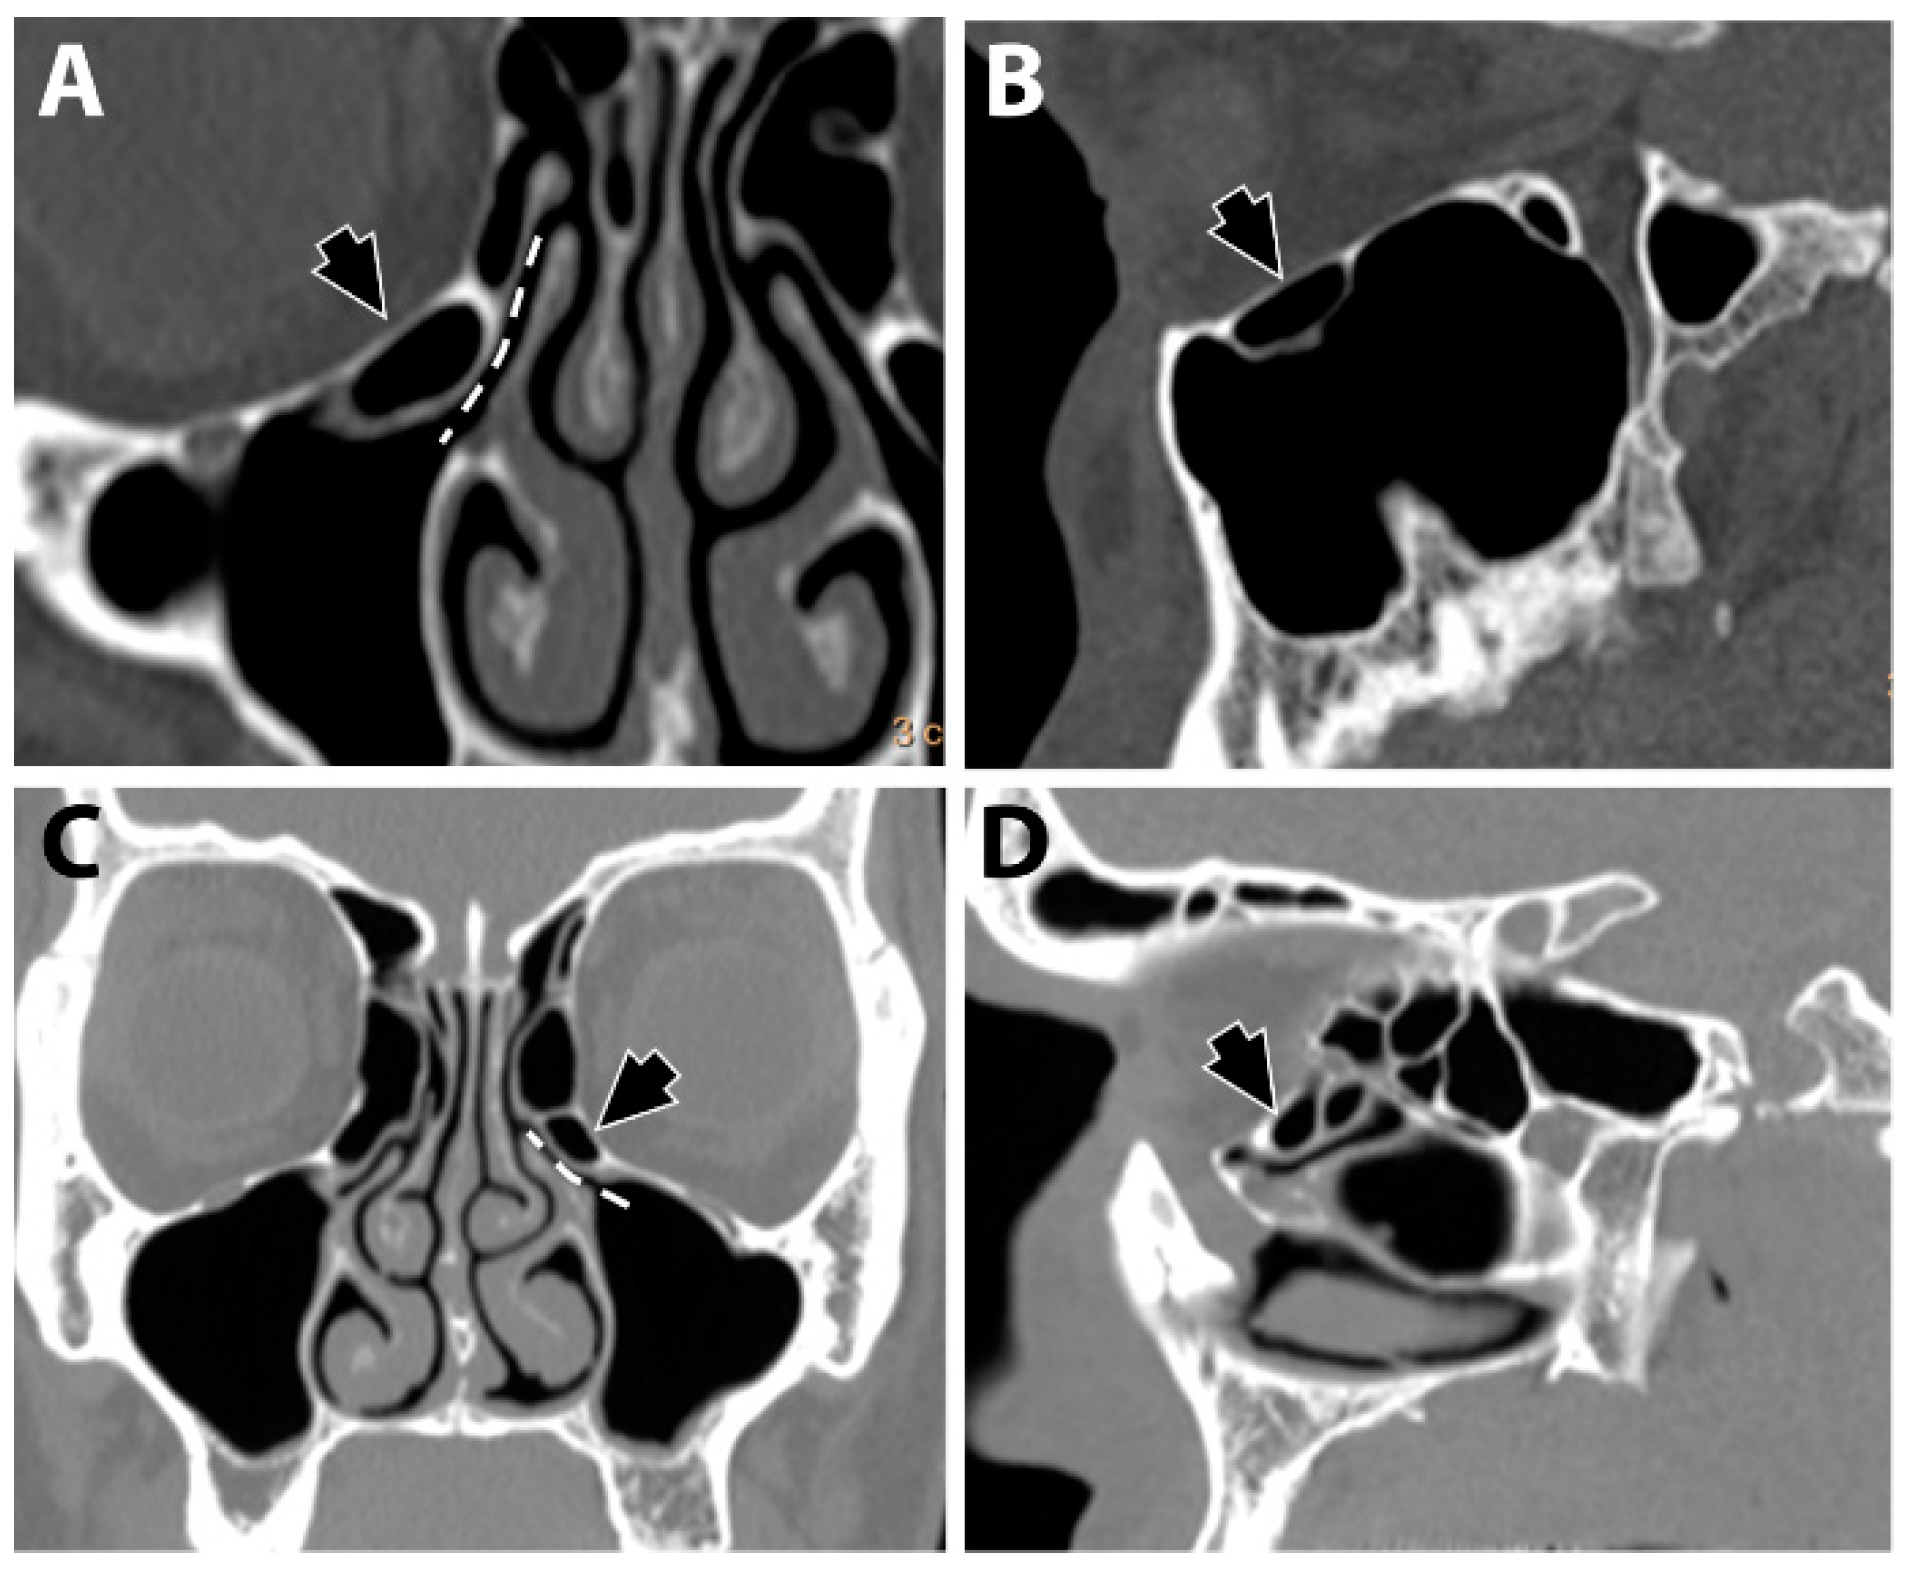

Infraorbital ethmoid cells were identified at the level of the infundibulum (Figure 1). The recorded cells fulfilled the criteria defined by Ahmad et al. [5] and were differentiated from the infraorbital recess of the maxillary sinus.

Figure 1.

Infraorbital ethmoid cells (black arrows). A Haller cell is shown in coronal (A) and sagittal (B) views. Convoluted bulla is shown in coronal (C) and sagittal (D) views. The dashed line (A,C) denotes the location of the infundibulum.